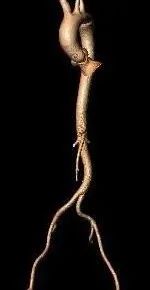

术前CT评估

三叶式主动脉瓣,瓣叶显著增厚伴轻度钙化,LVOT偏直筒;水平夹角约48°

腹主-髂总动脉少量钙化分布,股-髂动脉走行、内径可。